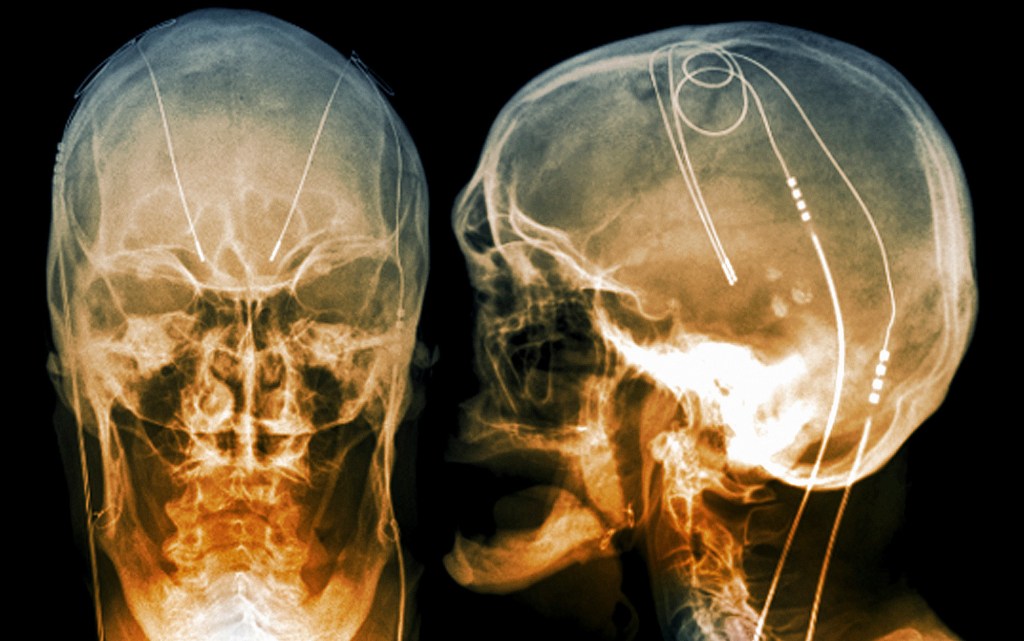

But today all that has changed. As the limitations and side-effects of psychopharmaceuticals became ever-more apparent, researchers began looking again at invasive neurostimulation – especially a safer, more precise version of the technology, called deep brain stimulation (DBS), which has been developed in the treatment of movement disorders in the decades since. The comparison between modern DBS and 1950s neurostimulation is stark. Early neurostimulation relied on an open method of surgery, involving the creation of a large opening in the skull, and an incision into the cortex to implant the electrodes, often leading to brain damage and infection. Inaccurate placement of electrodes was a serious risk.

By contrast, modern DBS surgery uses a ‘stereotactic’ frame that holds the patient’s head in place, and a computer-mapping system to generate a 3D representation of the patient’s brain. This can be used to identify neural structures, ensuring the precise placement of electrodes. In modern DBS, moreover, implanted electrodes are linked to a pacemaker-like device called an implanted pulse generator (IPG) under the collarbone. The IPG is programmed to send electrical impulses to the electrodes, personalising stimulation for that person alone.